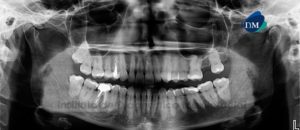

Paciente de 68 años de edad acude al Instituto de Diagnostico Maxilofacial para evaluación de general. A la evaluación de la radiografía panorámica, se aprecia